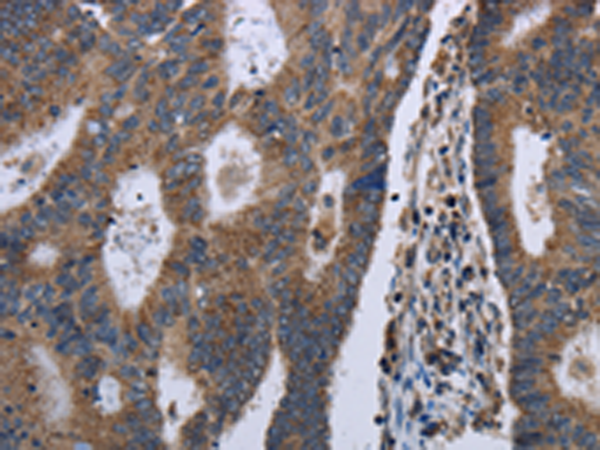

IHC positive control:

Human colon cancer and human liver cancer

IHC Recommend dilution:

50-200